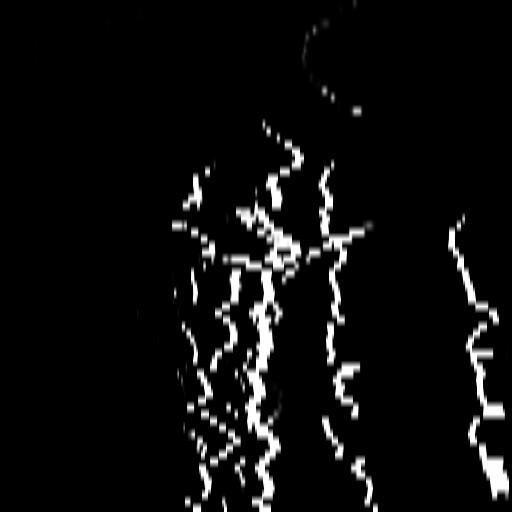

4.1 XACV Dataset

We collect 111 complete records of coronary artery X-ray videos, encompassing the injection, flow through the blood vessels around the heart, and dissipation of the contrast agent. Subsequently, we establish the XACV (X-ray Angiography Coronary Video) dataset. Each video consists of varying numbers of high-resolution coronary artery X-ray images. We invite experienced radiologists to annotate the vascular regions, focusing on one or two frames where the contrast agent is most prominent in each video. The XCAD dataset contains only a single image, and the CADICA video dataset does not provide corresponding ground truth. Therefore, in the following experiments, we conduct all the analyses on our collected XACV dataset and the corresponding GT for each sequence. In Figure 5, we show that compared to other publicly available datasets, XCAD [33] and CADICA [19], our dataset exhibits finer annotations in the vascular regions, providing an advantage for future related tasks. The development and use of our dataset have been approved by our institution’s IRB.